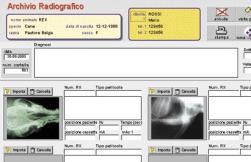

PONGO® e PONGO PLUS® - Versione 3.0

Software per la gestione dell’ambulatorio veterinario

Pongo® (versione 3.x.x) è il primo software di gestione ambulatoriale scaturito direttamente dall’esperienza pluriennale di medici veterinari liberi professionisti che hanno voluto un prodotto che soddisfacesse i seguenti requisiti:

•aggiornabilità facile da parte dell’utente per quel che riguarda le normative fiscali (tabelle aliquote, numerazione fatture, modifiche contabili, eventuale cambio di ragione sociale, passaggio di anno fiscale).

•autonomia gestionale da parte dell’utente in ogni sua parte

•totale adeguamento a qualsiasi richiesta dell’utente (contabile, fiscale, grafica, clinica, ...)

•compilazione e sviluppo su un database commerciale sicuro, garantito e multipiattaforma

•costo accessibile

con il patrocinio della

•garantito per l’anno 2000

Queste sono le premesse da cui è scaturito PONGO®, frutto della collaborazione tra medici veterinari (in particolare Andrea Pievaroli e Matteo Tommasini Degna), la TELE.MA.CO., software house con sede in Roma e la SCIVAC, che ne ha fornito le linee guida di sviluppo.

ILPROGRAMMAGESTIONALEADELEVATAPERSONALIZZAZIONECHERISOLVETUTTELEESIGENZEPROFESSIONALIDEGLIAMBULATORIVETERINARI

La versione del programma che viene ora commercializzata è utilizzata da oltre 2anni nella maggior parte degli ambulatori e delle cliniche veterinarie italiane con risultati eccellenti ed é diventato, in assoluto, il leader di mercato nel settore.

Caratteristiche salienti:

Gestione dati anagrafici clienti e dei loro animali

Stampa certificati predefiniti e modificabili dall’utente (es.Certificato antirabbica, buona salute, vaccinazioni etc.)

Stampa lettere ai clienti (con testi predefiniti e modificabili dall’utente); Ricerche multiple incrociate e facilitate nei campi del data base clienti e animali;le ricerche e le query sono possibili senza limitazioni per ogni campo dei vari databases.

Gestione cartelle cliniche (Esame Obb.Generale, Visita dermatologica, Oftalmologica, Ortopedica, Neurologica, Odontoiatrica, Esame Ecografico, Esami di laboratorio, Citologia, Istologia etc., Esame articolazione anca, Esame Cardiologico, Esame Radiografico) Stampa preventivi al cliente (con testi predefiniti e modificabili) Libretto vaccinazioni e stampa lettere al cliente per richiami

Gestione fatturazione, entrate, uscite, scorporo Iva-Enpav, ritenute acconto, prima nota automatica e scadenzari pagamenti Calcolo, gestione e stampa della Notula (o avviso di fattura)

Trasformazione automatica della Notula in fattura al momento del pagamento della prestazione

Ricerca e stampa statistiche di fatturato divise per tipo di prestazione

Gestione di più sedi (multifatturazione) prevista in tutte le versioni

Stampa e ristampa fatture sia in A4 che in A5 e Stampa bollati (Cronologico, Registro Fatture, Registro Uscite) sia in formato A4 che in 11” Preparazione registri bollati e stampa registri bollati delle fatture emesse, delle uscite, del cronologico e del magazzino.

Gestione studio e personalizzazione della struttura interna, inserimento professionisti interni ed esterni, definizione specie animali trattati, razze, tariffario, testi preventivi, testi certificati, valori laboratorio, vaccini utilizzati, fornitori e voci spesa.

Gestione carico e scarico farmaci e stampa registro bollato dei movimenti di carico e scarico di magazzino.

Gestione vaccinazioni e stampa mod.12

Possibilità di interfacciamento con apparecchiature (ecografi, endoscopi, fotocamere digitali, scanners etc) per la memorizzazione di immagini e filmati nel data base delle cartelle cliniche

Funzionante in ambiente Windows 95, Windows 98, Windows NT, Macintosh.

Il programma è configurabile anche in rete LAN Client Server (protocolli TCP/IP o IPX o Appleshare).

Assistenza hot-line professionale gratuita per i primi 12 mesi e facoltativa in seguito, a pagamento.

Versioni speciali:

Pongo PLUS: stesse caratteristiche del Pongo con in più:

AGENDA APPUNTAMENTI :Gestione completa di una Agenda appuntamenti, collegata alla lista Clienti, con possibilità di inserire, modificare, stampare e spostare automaticamente appuntamenti.

MAILMERGE Gestione lettere richiamo e testo certificati con testi definibili dall’utente e con i campi del database clienti, animali e vaccinazioni selezionabili ed inseribili all’interno dei testi.

Pongo LAN: versione multiutente rete di Pongo - Caratteristiche identiche a Pongo o Pongo PLUS per il funzionamento in rete locale(LAN Ethernet protocolli TCP/IP, IPX o Mac Appleshare).

prezzo di Pongo® riservato ai SOCI SCIVAC :

Pongo: Lit.750.000 - Pongo PLUS: Lit.850.000 (versioni monoutente)

I SOCI SCIVAC devono essere in regola con l’iscrizione per l’anno in corso prezzo di listino Pongo® per i non soci: Lit.1.500.000

inclusa garanzia e assistenza hot line 12mesi

I prezzi indicati sono al netto dell’IVA di legge